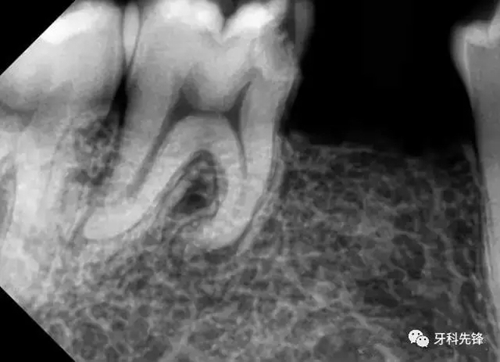

檢查: 男,23歲。46近中鄰咬合面齲洞,探痛(+),叩診叩痛(+),無病理性松動,X-ray示近中鄰咬合面暗影,近髓腔,牙根彎曲,根尖無明顯暗影,牙周膜增寬。